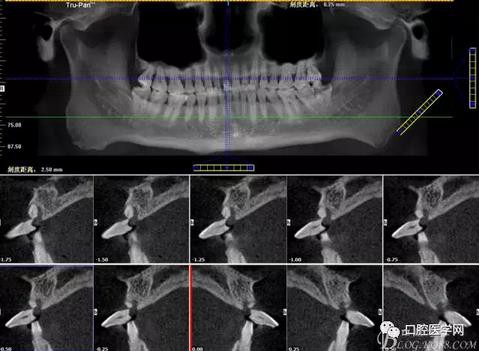

圖2 術(shù)前CT